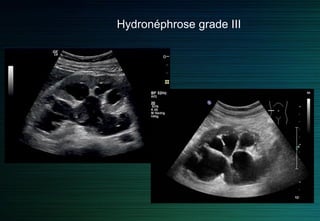

On différencie quatre grades d’hydronéphrose sur des critères échographiques

Grade 1 : dilatation du bassinet sans dilatation calicielle et épaisseur parenchymateuse normale.

Grade 2 : dilatation du bassinet et des calices avec amincissement du parenchyme.

Grade 3 : dilatation kystique du bassinet avec fin anneau du parenchyme.

Grade 4 : plus de parenchyme visible.

Hydronéphrose grade III